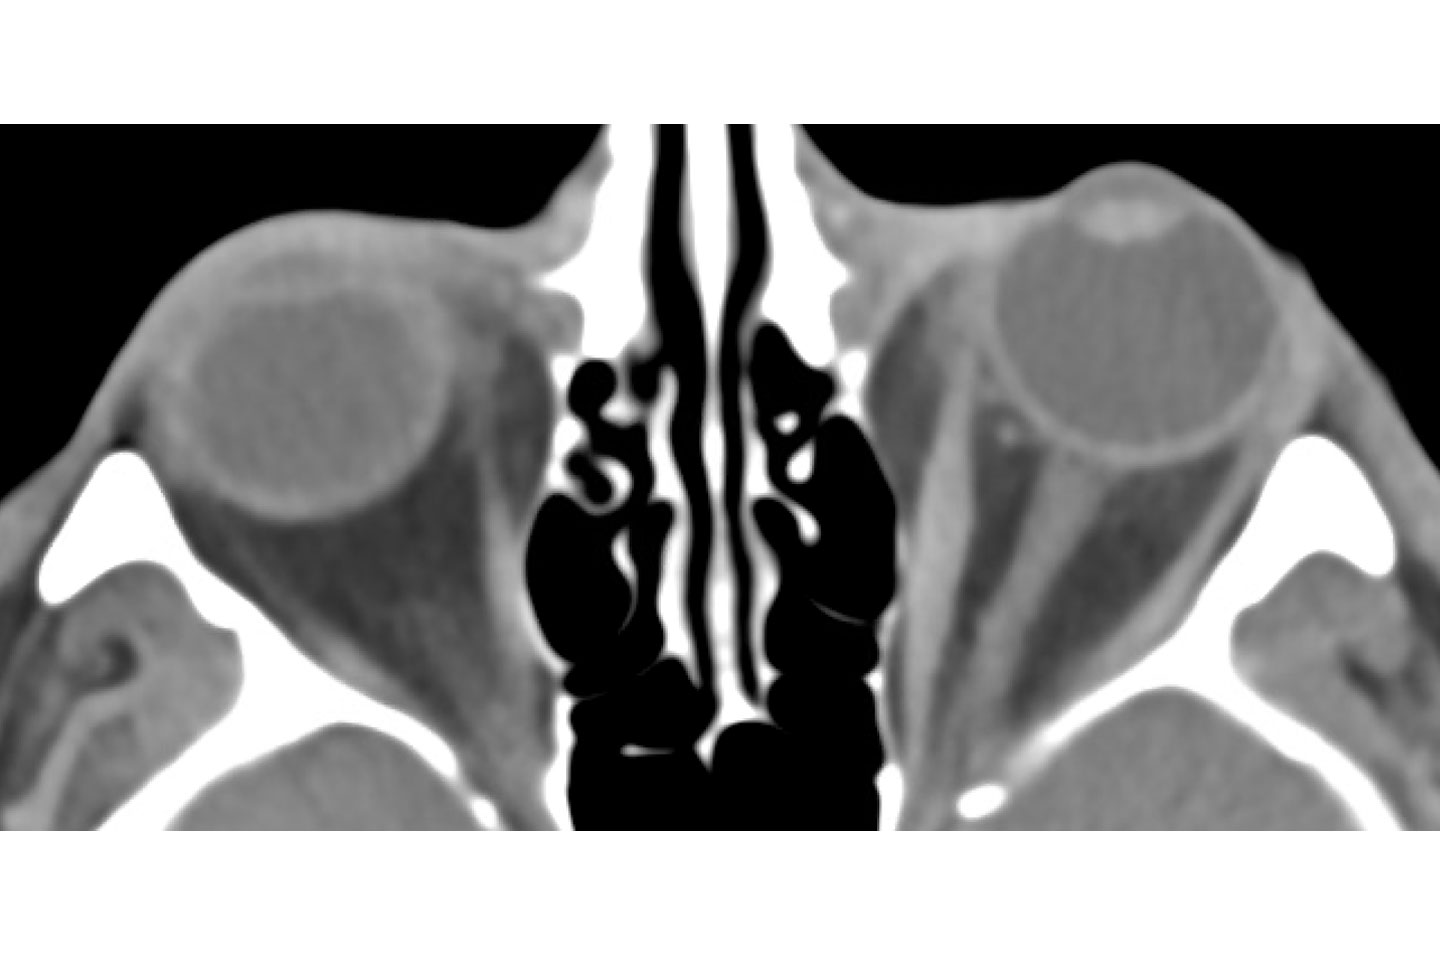

Axial postoperative imaging showing resolution of left exophthalmos. Source: NYU Langone Health